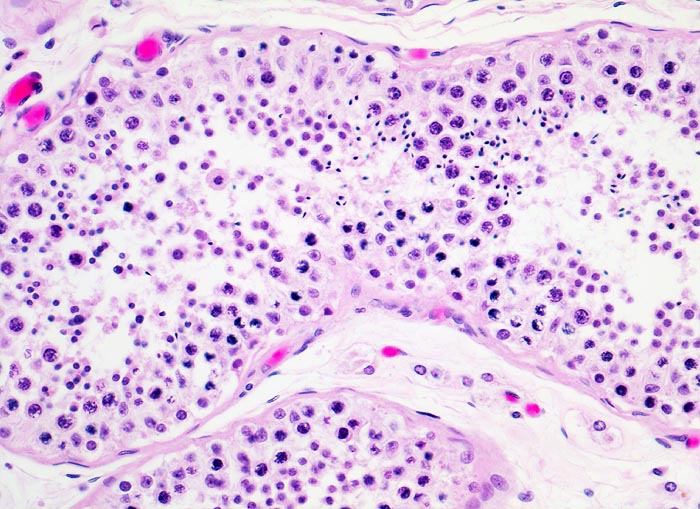

Makroskopisch imponieren Seminome als gut begrenzte weiche crèmefarbene Knoten oder diffuses Intiltrat. Mikroskopisch findet sich eine uniforme Population grosser Zellen mit prominentem zentralem Nukleolus, welche durch schmale Bindegewebssepten voneinander getrennte Nester bilden. Ein leukozytäres Entzündungsinfiltrat, synzytiotrophoblastäre Riesenzellen und Mikroverkalkungen können zusätzlich vorhanden sein. Gelegentlich induziert der Tumor eine ausgeprägte granulomatöse Entzündung. Dies kann zur Fehldiganose einer granulomatösen Orchitis führen.

• Unterschiedlich breite solide Tumorzellstränge aus monomorphen Zellen mit grossen hyperchromatischen Kernen und einem solitären zentralen prominenten Nukleolus. Reichlich helles Zytoplasma mit scharfen Zellgrenzen.

• Schmale bindegewebige Septen mit Kapillaren und lymphoplasmazellulärem Entzündungsinfiltrat.